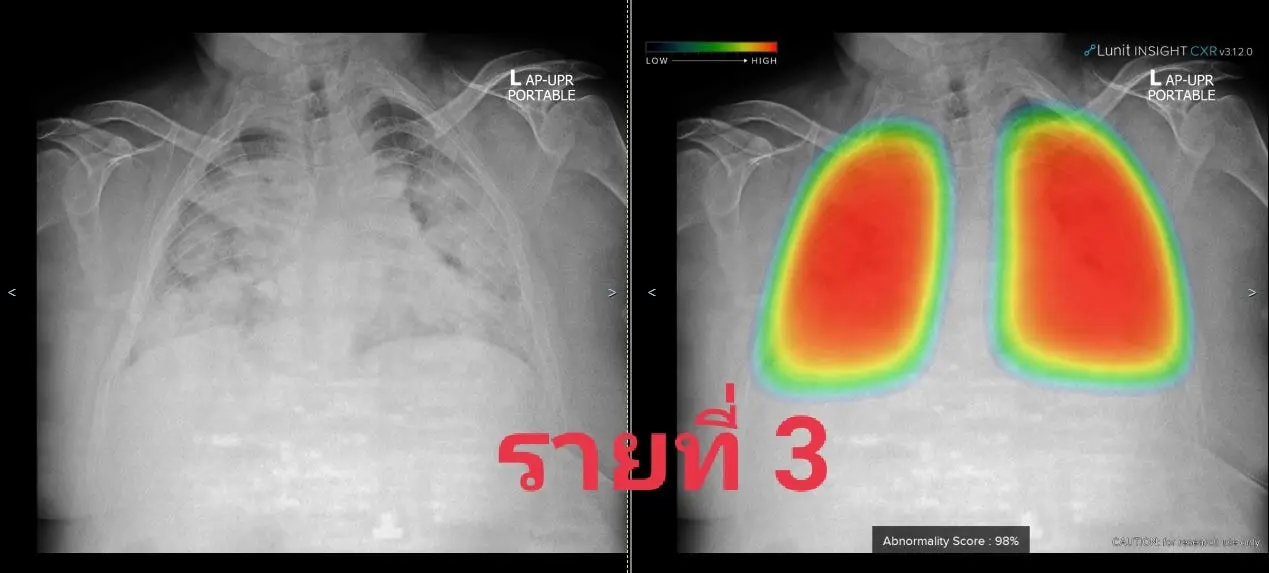

3. ชาย 44 ปีอ้วนมากและเพิ่งรู้ว่าเป็นเบาหวาน

ทั้งสามคนอยู่ในพื้นที่ท่าพระ-ภาษีเจริญ โดยติดเชื้อกันส่วนใหญ่หรือทั้งครอบครัว พวกเขามารพ.ศิริราชด้วยอาการของปอดอักเสบโควิดรุนแรง รายแรกต้องใส่ท่อช่วยหายใจขณะนำส่ง รายที่สองใส่ทันทีเมื่อถึงรพ. ส่วนรายที่สามใช้ไฮโฟลว์ได้พักหนึ่งแล้วไม่ไหวต้องใส่ท่อ

ทั้งสามคนต้องรอเตียงย้ายเข้าไอซียูโควิดกันไม่น้อยกว่า 12 ชม. โชคดีว่าทีมเราเอาท่อช่วยหายใจผู้ป่วยออกได้สี่คนในช่วงสองวันนี้และย้ายออกไปได้สามคน จึงทยอยรับทั้งหมดเข้ามาไอซียูโควิดที่ทีมเราดูแลได้ แต่หากมีรายแบบนี้มาอีกคงหาจังหวะเหมาะเจาะเช่นนี้ไม่ได้อีกแล้วลองดูเอกซเรย์ปอดกันหน่อย พบมีฝ้าขาวเวอร์กระจายทั่วปอดในทุกคน จนเจ้า AI ที่ช่วยงานเรายังให้สีแดงแจ๋บ่งถึงรุนแรงน่ากลัวมาก